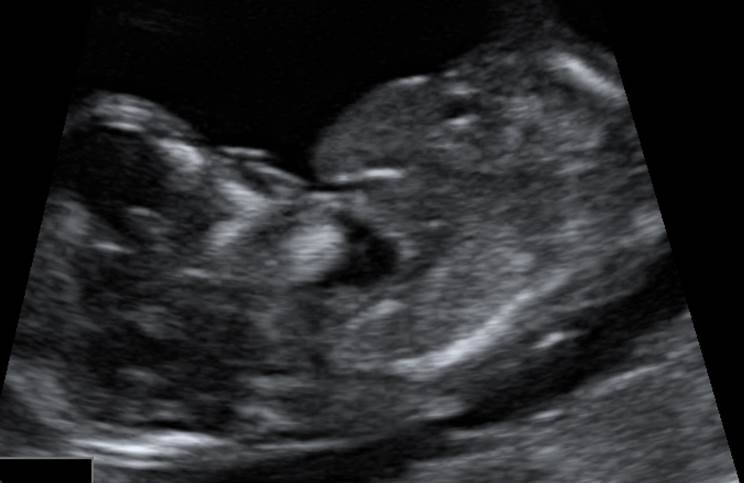

Вопрос 1

12 недель. Какая патология?